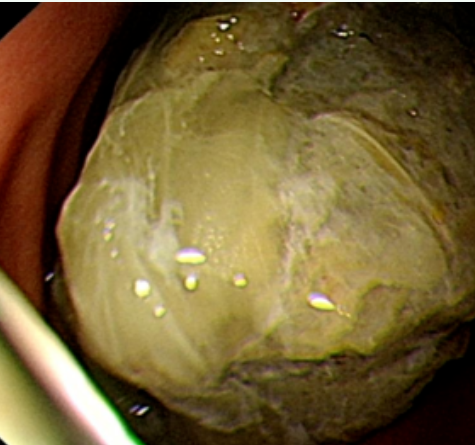

通过胃镜检查,消化内科医生张超发现安女士胃腔内有两枚直径约8*6cm褐色固体。 据了解,安女士平时喜欢吃山楂,尤其近一个月以来吃得比较多,一吃起来就刹不住车。张超医生分析,这应该是临床上多见的植物性胃结石。另外,胃蠕动功能减退及幽门狭窄等可致胃排空减慢也是胃结石形成的因素。

安女士没有想到自己贪吃山楂会惹上这样的麻烦,既懊恼又害怕。由于结石过大,必须通过手术碎石,与家属沟通后,我院消化团队共同制定取石方案,由于筹划得当,技术过硬,30分钟便成功将安女士体内胃结石碎化。